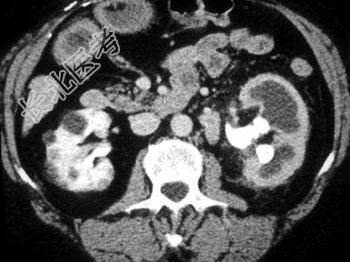

- 单项选择题根据所提供的图像,最可能的诊断是 ( )

A、鹿角状结石

B、肾盂积水

C、肾动静脉畸形

D、黄色肉芽肿性肾盂肾炎

E、肾盂旁囊肿